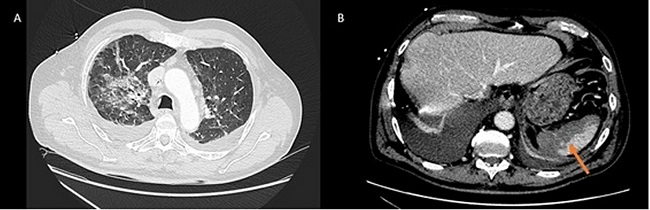

In light of the deterioration, a continuous renal replacement therapy began and a contrast Thoracoabdominal tomography was made. Ground glass infiltrations were observed in both pulmonary parenchyma and the lack of contrast of a significant proportion of the splenic parenchymal, radiologically compatible with infarct (Figure 1).

Figure 1: Computed tomography. Bilateral pulmonary infiltrates (Image A) Image compatible with splenic infarction (Image B).